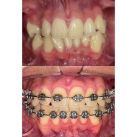

1- El tratamiento puede realizarse a cualquier edad: cuando tenemos dientes temporarios o mixtos, realizamos ORTOPEDIA, es decir, utilizamos las fuerzas musculares que actúan sobre el hueso corrigiendo el defecto a nivel esqueletal estimulando el correcto crecimiento; cuando tenemos solo dientes permanentes realizamos el tratamiento de ortodoncia fija con brackets.

7- No siempre se instalan los brackets en ambos maxilares (arriba y abajo) el mismo día, esto varía según el caso.